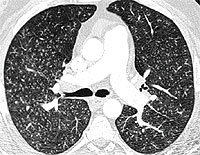

An 80 yr white female presents with four years of dyspnea on exertion, several months of dry cough with one episode of hemoptysis, and unintentional 20 lb weight loss over the past 2 years. She is a nonsmoker. She denied having night sweats, fever, or chills. Her PPD has always been negative, and she worked in an office her entire life. Her physical exam was unremarkable without peripheral adenopathy and clear lungs. Representative chest CT slices are shown:

Bronchoscopy and BAL were performed. BAL showed acid fast positive organisms identified as M. Avium Intracellulare.

Diagnosis

MAI infection. The term "Lady Windermere Syndrome" was first used to describe the infection in elderly women by Reich, et al in 1992. They reported a series of 6 elderly white females with previously healthy lungs who developed MAC lung disease limited to the right middle lobe and lingula. It's unclear what predisposes these patients to infection, but one theory is that voluntary cough suppression in these "prim and proper" ladies leads to poor mucus clearance and increased chance of infection in the already dependent RML and lingula.